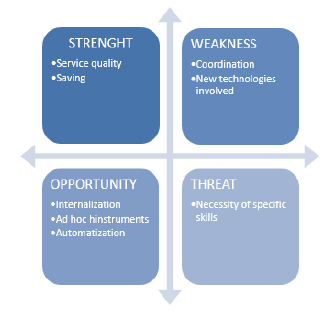

In this paper a SWOT Analysis was performed to analyze the innovative procedure, to discuss its strengths, weaknesses, external threats and possible future developments [3]. It should be noted that 3D printing is used in the medical field with countless purposes including the creation of prostheses and the use of reconstructions for educational purposes. However, in this paper we will only use the 3D printing technique for the three - dimensional reproduction of feet of patients suffering from the disease of the flat foot from tarsal synostosis in order to improve the process of diagnosis and treatment of the specific pathology. The state of the art was carried out based on the well know flat feet pathology [4] and the 3D model steps were tested for a different geometry case to allow a better time/cost analysis.

S.W.O.T. Analysis

Strength

Usually when we talk about innovative technologies, we expect to face high costs for realization and/or use. In the case analyzed in the paper, however, the advantages that the introduction of 3D printing brings to the procedure not only allow to cover the production costs, but also to save money compared to the expense foreseen by the traditional procedure. This is possible not only thanks to the reduction of the times of some activities such as the surgery, but also because the cost of model realization is cheap. The improved quality of the procedure has a strong impact on both the patient and the doctor. The first sees the reduces the number of visits, he achieves greater awareness of his surgery and reduces the exposure to X-rays. The second testing the procedure on the prototype, can well-define the surgical plan more precisely improving the surgical outcome.

Weakness

The coordination between the doctor and the mechanical engineer is a weakness point. The right collaboration is needed for the success of the prototype in order to avoid inconsistencies with the actual anatomy of the bone reproduced. The optimal solution would be to entrust the realization of the model to professional operator expert both in the medical and engineering fields. If the two figures are different, physical proximity could be sufficient to simplify communication solving uncertainty during the 3D surface cleaning phase. Moreover, the introduction of the 3D model within the medical workflow requires a higher awareness of 3D printers and printing materials in order to choose the most suitable combination of them for the specific purpose.

Threat

Surgeons, radiologists and engineers must develop new skills and assume new roles. The risk is that without a specific training of the personnel on used software and hardware could cause a wrong implementation of the new methodology leading to higher costs and times.

Opportunity

One opportunity is the internalization of the prototype realization procedure. Coordination is one of the fundamental factors for the success of the procedure, merging this step in one would improve the workflow.

The 3D printing process could be helpful in realization of patient- specific instrument (PSI) involves the use of CT associated to methods of “rapid prototyping”. A specific cutting guide could be a possible implementation of PSI. Custom tools can increase both the operating accuracy and reduce operating times (Figure 17).